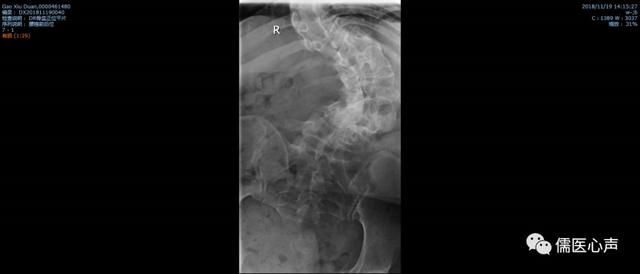

病例二,高某,女,39岁 ,工人,因“腰痛10余年,加重伴右膝痛2年”于2018-11-19以“1.腰椎间盘突出症2.脊柱侧弯3.脊髓灰质炎后遗症”收住入院。

专科检查:脊柱下胸段及腰段呈明显左凸侧弯畸形,腰椎活动度检查:前屈30°腰部疼痛(+),后伸10°疼痛(++),右侧屈25°疼痛(+),左侧屈25°,左右旋转30°,L3-5棘突间及椎旁右侧压痛(+),叩痛(-),右侧腰方肌肋缘、髂嵴附着点压痛(+),无明显放射痛,左下肢较右下肢短缩约3cm,左臀部及左下肢肌肉萎缩,肌力4级。

入院后结合症状、体征、影像、舌脉综合分析,该患者先天畸形所造成的器质性改变已无法纠正,该患者出现的一系列疼痛症状,与脊柱严重畸形造成椎周软组织慢性损伤有关,尤其是右侧腰方肌的扭曲牵拉,小针刀松解术通过对软组织的松解,相对纠正了力线失衡,解除了对相关神经的刺激,同时结合中药内服补益肝肾、活血通经;针灸治疗通阳理气、舒筋活络等治疗,患者腰痛症状基本消失,随访一年无复发。

老年结构性脊柱侧弯正位片。